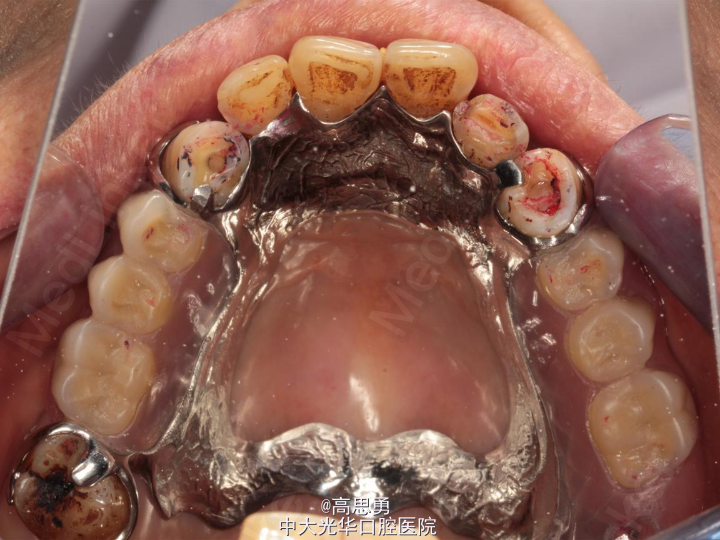

5、试戴支架 检查支架的就位、固位可,无翘动,调HE,抛光,用蜡堤取颌位关系,上颌架,排牙,比色C4。

6、试排牙 检查义齿的就位、固位可,无翘动,观察人工牙的咬合状况,尖窝接触良好,正中颌位能重复,患者无诉不适,面容自然,外观满意。送加工厂充胶制作最终修复体。

7、试戴 检查义齿的就位、固位可,无翘动,咬合关系正确,利用咬合纸检查,上下颌尖窝接触均匀全面,抛光,患者表示满意,嘱注意事项,定期复诊。